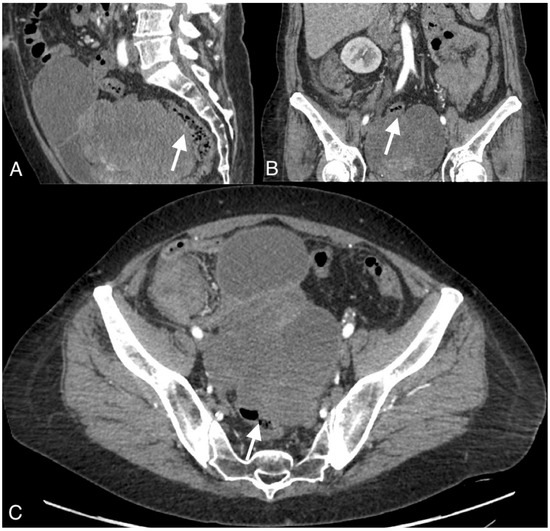

Figure 2.

Images of a 54-year-old patient with an ovarian cancer recurrence in the form of the fistula between the tumor and rectum. CT obtained in the coronal (A), sagittal (B), and axial plane (C) shows large pelvic tumor with adjacent rectum.